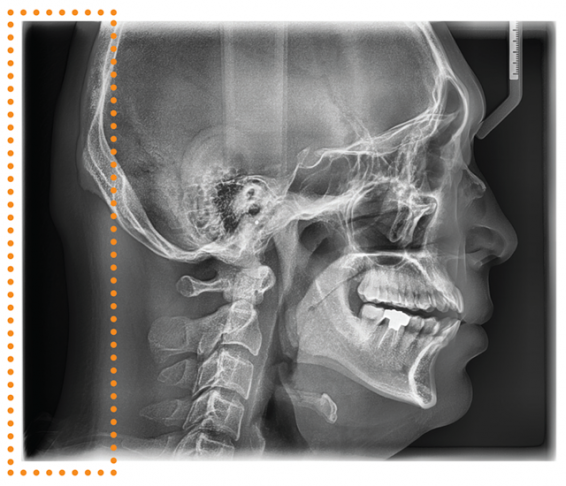

CEPHALOMETRIC (SCAN CEPH)

The PaX-i provides optimal images exclusively designed for orthodontics.

There are two image sizes available, Lateral and Full Lateral, allowing you to choose your image size based on your diagnostic needs.

CEPHALOMETRIC (SCAN CEPH)

The PaX-i provides optimal images exclusively designed for orthodontics.

There are two image sizes available, Lateral and Full Lateral, allowing you to choose your image size based on your diagnostic needs.

LATERAL

Provides specialized high quality images to suit orthodontics and maxillofacial surgeries

FULL LATERAL

A full lateral image size is 30% wider and shows the occipital area of the patient, which enables comprehensive diagnosis.

LATERAL

Provides specialized high quality images to suit orthodontics and maxillofacial surgeries

FULL LATERAL

A full lateral image size is 30% wider and shows the occipital area of the patient, which enables comprehensive diagnosis.

ONE SHOT CEPH

With One Shot Ceph, you can acquire high quality images with low x-ray dosage. Plus, short scan time markedly reduces motion artifacts.

ONE SHOT CEPH

With One Shot Ceph, you can acquire high quality images with low x-ray dosage. Plus, short scan time markedly reduces motion artifacts.

The PaX-i provides optimal images exclusively designed for orthodontics.

There are two image sizes available, Lateral and Full Lateral, allowing you to choose your image size based on your diagnostic needs.

LATERAL

OP (One Shot Premium)

30x25cm (12×10″)